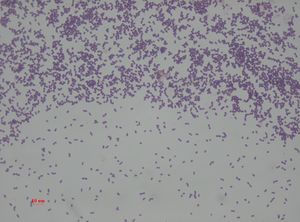

Enterococcus faecalis – formerly classified as part of the group D Streptococcus system – is a Gram-positive, commensal bacterium inhabiting the gastrointestinal tracts of humans and other mammals.[1] Like other species in the genus Enterococcus, E. faecalis is found in healthy humans, but can cause life-threatening infections, especially in the nosocomial (hospital) environment, where the naturally high levels of antibiotic resistance found in E. faecalis contribute to its pathogenicity.[1] E. faecalis has been frequently found in reinfected, root canal-treated teeth in prevalence values ranging from 30% to 90% of the cases.[2] Re-infected root canal-treated teeth are about nine times more likely to harbor E. faecalis than cases of primary infections.[3]

This is a Gram stain for Enterococcus faecalis under 1000 magnification (bright field microscopy)